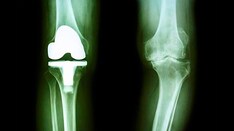

Background: Knee arthroplasty is an orthopedic surgical procedure in which a damaged joint is replaced with an artificial one. It is estimated that 1–2% of knee arthroplasties will encounter infection over their lifetime. Although α-hemolytic Streptococcus species play an important role in prosthetic joint infection, they are less common than staphylococcal species.

Case Presentation: In this report, a 50-year-old Iranian woman was diagnosed with prosthetic knee joint infection based on clinical, radiological, and laboratory findings. She was diabetic and had undergone a left total knee arthroplasty, which, 18 months after the surgery, presented pain, erythema, and edema in that knee. The primary culture of knee aspirate was positive for α-hemolytic Streptococcus species, but following antibiotic medication, culture was negative. The primary antibiotic regime was vancomycin and meropenem, which was changed to cefepime for the management of the infection based on the results of antimicrobial susceptibility testing.